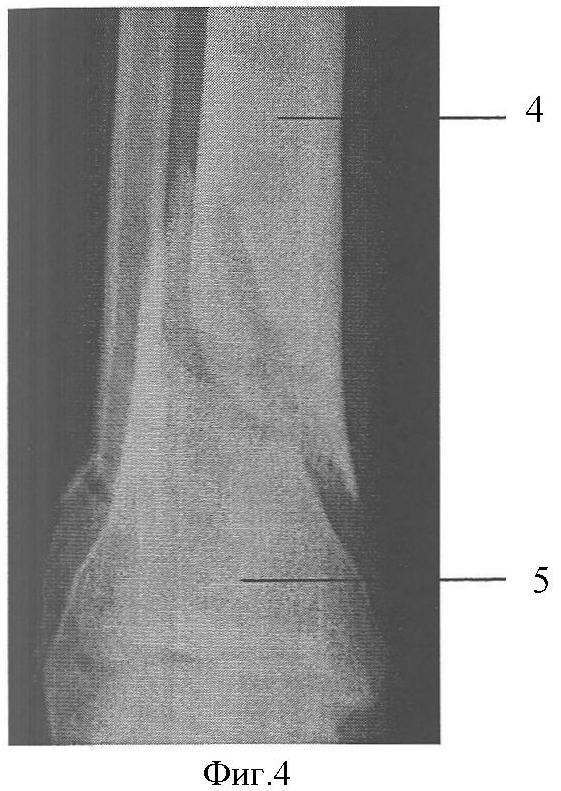

Фиг.4. Исходная рентгенограмма в прямой проекции.

Клинический пример: Пациентка А., 43 лет. Диагноз: Закрытый перелом дистальных метафизов обеих костей правой голени (фиг.4, 5). Произведена операция (фиг.8, 9), при этом после внедрения стержня 2 интрамедуллярно под контролем электронно-оптического преобразователя проведены репозиционно-блокирующие винты 3 через костные отломки 4, 5 и резьбовые отверстия 1 в стержне 2, при установке винтов 3 (фиг.3, 6, 7) достигнута компрессия отломков 4, 5 с устранением остаточных их смещений за счет притягивания отломков 4, 5 к стержню 2 головками винтов 3 и достигнута окончательная репозиция и полиаксиальная жесткая стабилизация отломков 4, 5, исключающих возможность смещений отломков 4,5 после установки металлоконструкции и в послеоперационном периоде. Винты 3 выполнили как репонирующую, так и блокирующую роль. Полная нагрузка на ногу после операции (фиг.10). Срок нетрудоспособности 4 недели.